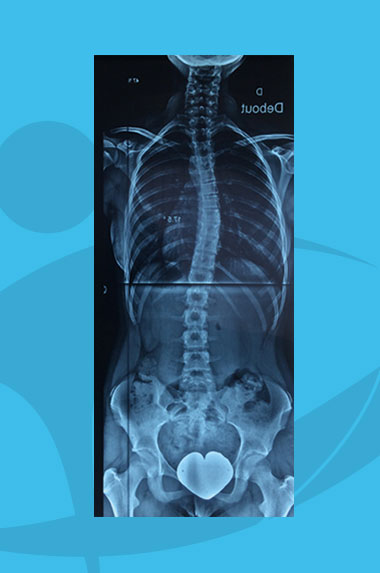

Cobb (angle de) :

angle formé par les 2 parallèles aux plateaux des vertèbres les plus inclinées sur l’horizontal aux extrémités de la courbure scoliotique.

Gibbosité :

bosse produite par une déformation de la colonne vertébrale.

Test de Risser :

test permettant d’apprécier la maturité osseuse au niveau des crêtes iliaques